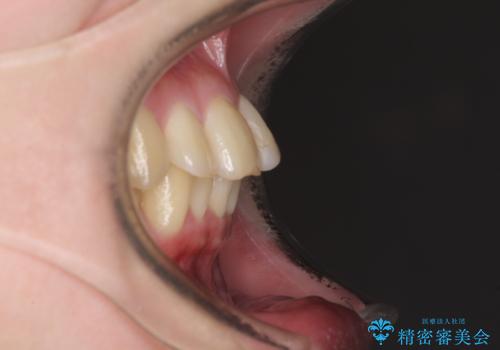

- 前歯の著しい叢生と前突感を気にして来院された患者様です。

叢生が強いため、事前に前歯をワイヤー矯正で速やかに叢生を解消し、その後はインビザラインにて矯正治療を行うこととしました。

ワイヤー矯正を併用したことで前歯の叢生を速やかに解消することができました。

一方口元の突出感を改善するために時間がかかり、2年超を要しましたが、満足のいく仕上がりとなりました。